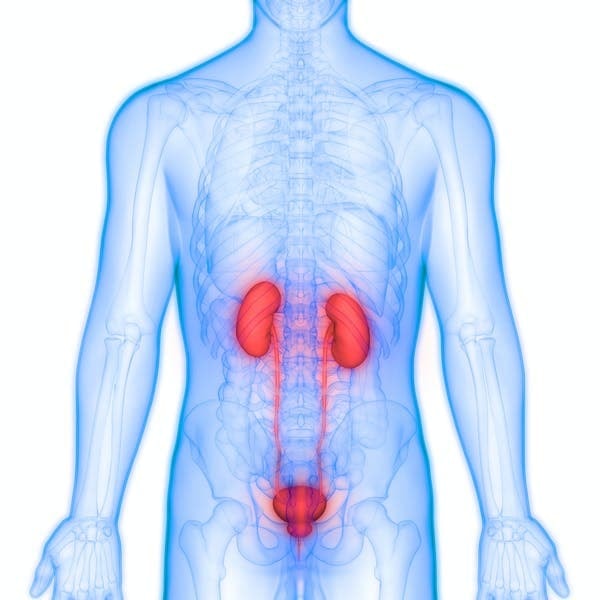

Thận là một bộ phận quan trọng trong cơ thể. Chúng đảm nhiệm nhiều chức năng khác nhau bao gồm duy trì huyết áp và cân bằng dịch, điều hòa nồng độ điện giải trong cơ thể, loại bỏ chất thải dư thừa được sản xuất bởi các hoạt động trao đổi chất của cơ thể, và giúp chúng ta đi tiểu dễ dàng.

Mỗi quả thận có chứa 1,2 triệu đơn vị thận dạng ống (gọi là nephron). Có khoảng 120 lít chất lỏng và chất hòa tan đi vào trong các đơn vị thận để nó thực hiện nhiệm vụ lọc mỗi ngày.

Tất cả những chất thải này sẽ được đưa đến bàng quang để thoát ra ngoài cơ thể khi đi tiểu. Ngoài lọc máu, thận còn giúp xương khỏe mạnh, cho cơ thể biết thời điểm tạo ra các tế bào máu mới và thậm chí giúp bạn đứng thẳng khi đi lại cả ngày bằng cách quan tâm đến huyết áp của bạn. Với tất cả những chức năng quan trọng đó, các nhà khoa học cho rằng việc có hai quả thận rất quan trọng đối với sự sống còn của chúng ta.

Mỗi quả thận có chứa 1,2 triệu đơn vị thận dạng ống (gọi là nephron). Có khoảng 120 lít chất lỏng và chất hòa tan đi vào trong các đơn vị thận để nó thực hiện nhiệm vụ lọc mỗi ngày.

Khi cơ thể chỉ còn một quả thận, nó có thể tự điều chỉnh hiệu suất hoạt động để đảm bảo hoàn thành nhiệm vụ lọc như khi còn 2 quả. Khi đó, để bù đắp quá trình xử lý chất thải thừa của quả thận đã mất, các đơn vị thận trong quả thận còn lại sẽ tăng kích thước lên, hiện tượng này được gọi là phì đại và không có tác dụng phụ ngay cả trong nhiều năm sau.